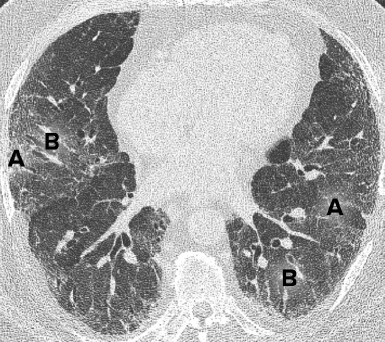

图 3. 一位特发性肺纤维化患者的轴位 CT 扫描图像。显示肺纤维化伴胸膜下蜂窝状改变(A)、和牵引性支气管扩张(B),为普通型间质性肺炎的典型表现。

图 4. 一位非特异性间质性肺炎患者的轴位 CT 扫描图像。显示磨玻璃影(A)、和牵引性支气管扩张,无蜂窝状改变。